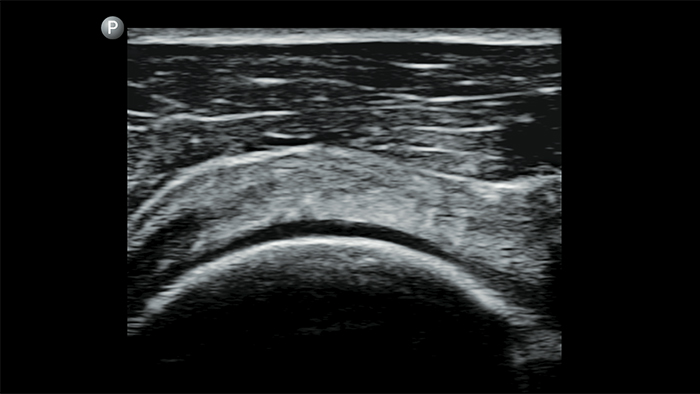

System Lumify do badań POCUS może służyć do wykrywania rurki dotchawiczej w tchawicy, pomagać podczas pilnych zabiegów konikotomii, diagnostyce wysięku opłucnowego oraz chorób pęcherzyków płucnych.

System Lumify do badań POCUS może być niezwykle cennym narzędziem do oceny stanu treści żołądka, które może obniżyć ryzyko jej aspiracji do płuc, a tym samym ryzyko powikłań po zastosowaniu znieczulenia.